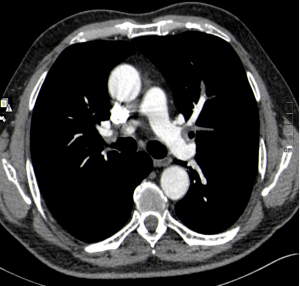

Actualmente, el Angio-TAC es el método diagnóstico más empleado para confirmar un TEP, y es la primera opción siempre que se encuentre disponible, al presentar una sensibilidad de 83-90% y especificidad de 90-96%. Permite, además, valorar el parénquima pulmonar y otras estructuras torácicas que puedan causar el cuadro del paciente.

Se realiza TAC torácico al paciente, con contraste intravenoso y protocolo angiográfico. Los hallazgos se muestran en las siguientes imágenes. ¿Cuál es el principal hallazgo radiológico que se observa?: